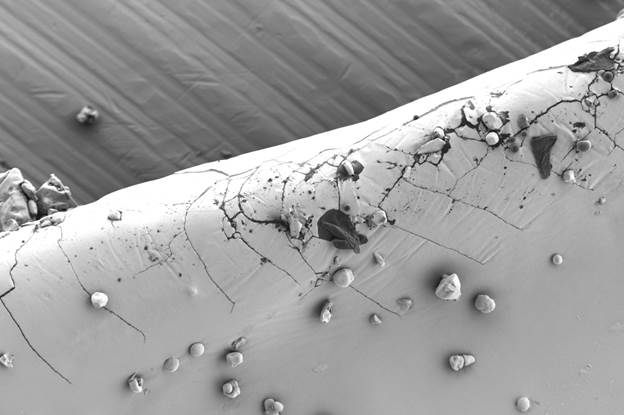

Так, при плановой проверке качества капсул с сульфатом глюкозамина с помощью оптического микроскопа были обнаружены мелкие дефекты на поверхности. Последующий анализ на СЭМ при высоком увеличении выявил микротрещины и прикрепленные пластинчатые частицы неправильной формы (рис. 1а). Морфология трещин указывала на их возможное происхождение в результате коррозии под напряжением, связанной с неравномерной сушкой покрытия и релаксацией полимерных напряжений. Инородные частицы по своей структуре (рис. 1b — чистая поверхность) отличались от матрицы капсулы.

Сопоставление с типичными микроорганизмами позволило исключить биологическую природу загрязнения; наиболее вероятным источником была признана неорганическая пыль из производственной среды или вспомогательных веществ. Эти данные послужили основой для корректировки режимов нанесения покрытия и ужесточения контроля чистоты в производственных помещениях.

Рис. 1а — Поверхность капсулы с сульфатом глюкозамина: визуализированы пластинчатые включения и микротрещины; загрязнения проникают в трещины. Изображения получены с помощью микроскопа LANSEM 30.